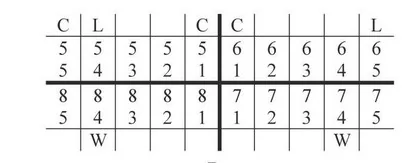

Instrumentem przedstawionym na ilustracji stosowanym w chirurgii stomatologicznej jest

| 1 | 1 | 1 |

| 17-14 | 13-23 | 24-27 |

| 47-44 | 43-33 | 34-37 |

| 1 | 3 | 1 |